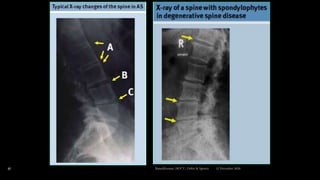

Radiographic features

 Sacroiliac joint –

 Erosion & sclerosis of bone near the articular

surface

 Ankylos later

 Spine –

 Apophyseal joint erosion

 Squaring of the vertebral bodies with ossification of

disc margins

 Syndesmophytes

 “Bamboo Spine” due to calcification of longitudinal12 December 2020Ratankhuman (M.P.T., Ortho & Sports)

Radiology cont...

 Vertebral column often shows –

 Bony sclerosis with squaring of vertebral bodies

 Ossification of annulus fibrosis with syndesmophytes.

 This might lead to fusion of vertebral column with a classical

“Bamboo Spine”.

 Involvement of hip & shoulder joints –

 Joint space narrowing can be detected by conventional X-rays.

12 December 2020Ratankhuman (M.P.T., Ortho & Sports)